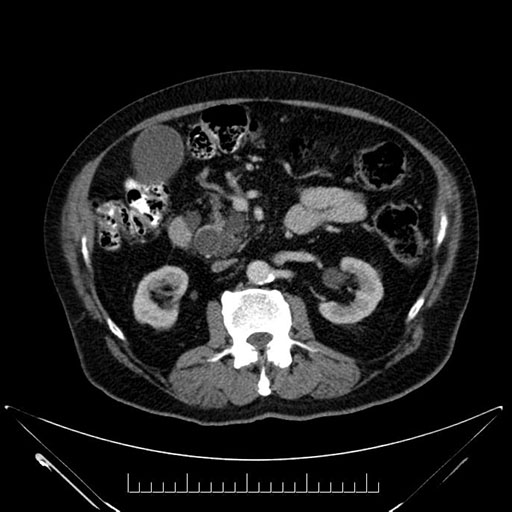

Imaging Analysis

Look through the patient's CT scan to identify any areas of concern for the necessary procedure.

Based on your CT findings, which issue(s) would give reason for "planned slowing down moment(s)" in this case?